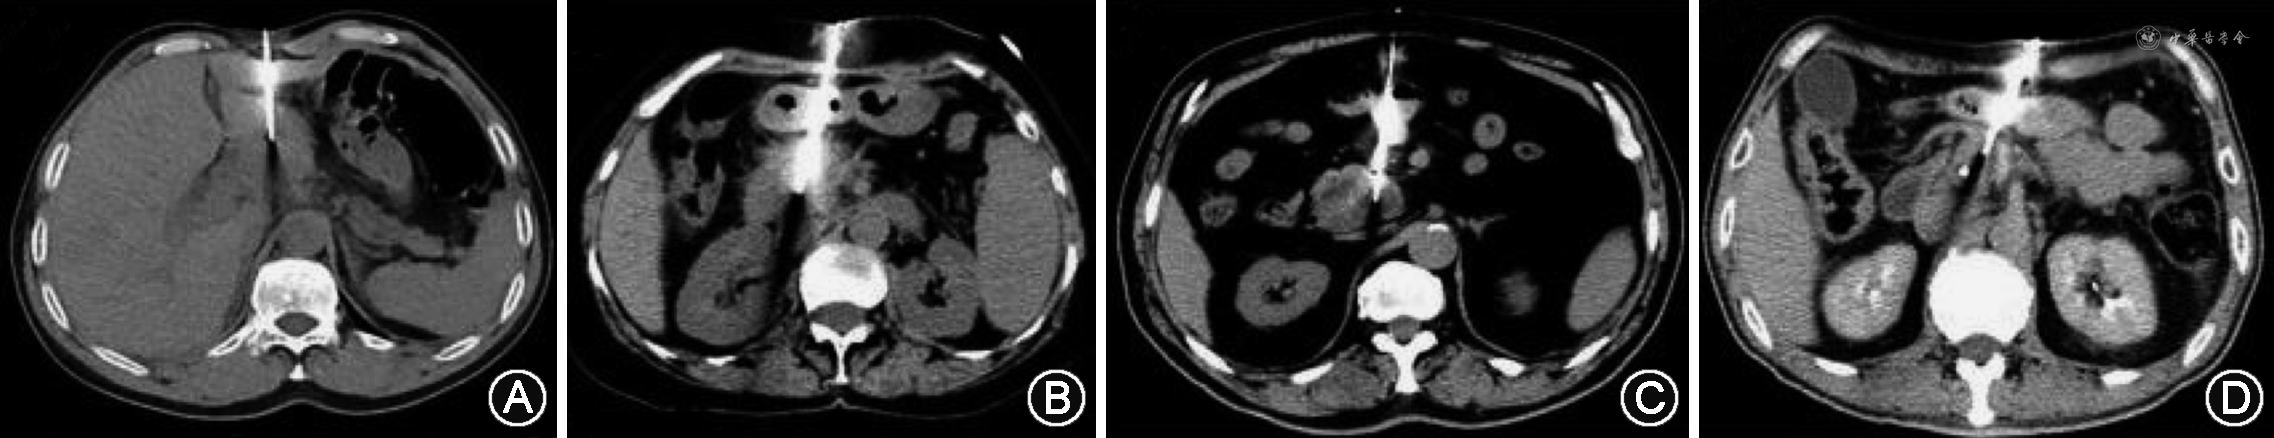

回顾性分析郑州大学第一附属医院2019年1月至2022年1月接受CT引导下经皮穿刺活检胰腺占位患者的临床资料。(1)纳入标准:①术前影像显示胰腺占位病变,需要明确病理诊断;②影像考虑恶性病变,需要进行放疗、化疗等抗肿瘤治疗;③影像学无法明确诊断;④穿刺活检后接受手术治疗、抗肿瘤治疗或随访期间明确诊断;⑤经皮穿刺活检后检查、检验资料完整。(2)排除标准:①各种方式均无法明确诊断;②无随访结果;③活检后检查、检验资料不完整。根据纳入标准、排除标准,采用连续纳入方法共纳入367例患者,其中男211例,女156例,年龄18~87(60.7±11.8)岁。根据术中是否经腹腔脏器分为经脏器路径(图1)组[142例,其中男84例,女58例,年龄18~86(60.6±12.6)岁]和非经脏器路径(图2)组[225例,其中男127例,女98例,年龄21~87(60.7±11.3)岁]。经脏器路径组中有28例(7.6%)经肝、57例(15.5%)经胃、24例(6.5%)经小肠、33例(9.0%)经结肠。本研究通过郑州大学第一附属医院伦理委员会许可(2022-KY-597),患者知情同意豁免。

1. 路径选择:术中根据病变位置选取体位,CT扫描(必要时行增强扫描),结合术前增强CT或MRI确定穿刺路径,应用2%利多卡因进行局部浸润麻醉。根据术中CT扫描图像设计穿刺路径,若有非经脏器路径则选择非经脏器路径;若穿刺路径被脏器遮挡,无法避开时则选择经脏器路径。常用的经脏器路径包括经肝脏、胃、小肠和结肠。

2. 进针方法:所有操作均在CT引导下采用“分步进针”方法进针。非经脏器路径可采用“迂回”进针、钝针分离或水分离等技术避开脏器。经脏器路径:第一步进针穿刺至腹膜,确定进针方向;第二步穿刺至危险脏器边缘再次确定进针方向;第三步穿刺拟要经过脏器;第四步穿刺靶病变。进行操作时,避免反复多次地穿过脏器,例如在进行调整进针方向时,避免退至经过脏器外;在进行切割活检时,要确定同轴穿过肠管或胃壁,避免活检枪切割肠壁或胃壁。